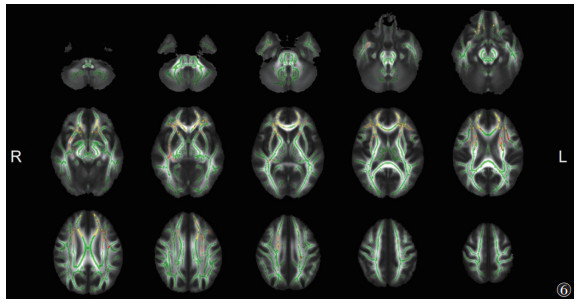

与EMTB组相比,ITB组脑白质显示出较广泛的FA降低和MD升高(P<0.05,TFCE和FWE校正)(图 5,6),其范围小于ITB组与HC组之间的差异。其中胼胝体膝部、双侧前放射冠等同时出现FA降低和MD升高(图 7)。

![]() |

| 注:与EMTB组相比,ITB组脑白质MD升高的区域显示为暖色(P<0.05,TFCE和FWE校正)。脑白质骨架显示为绿色。L,左;R,右 图 6 ITB组与EMTB组MD的差异 |